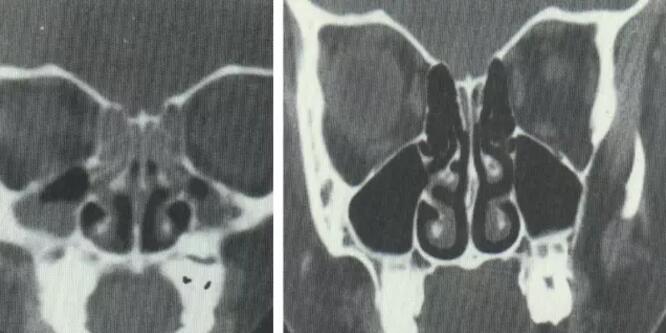

鼻中隔偏曲

高位弯曲压迫中鼻甲

同侧中鼻道、嗅沟引流障碍

阻塞性鼻窦炎

对侧中、下鼻甲增生